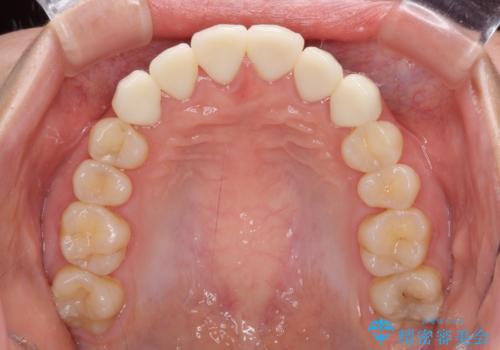

- コンポジットレジンによる治療で継ぎ接ぎだらけになってしまった前歯を綺麗にしたいとのことで来院された患者様です。

必要に応じて根管治療を行い、前歯6歯をオールセラミッククラウンで補綴することとしました。

治療途中に出産を迎えるため、下顎前歯のデコボコを部分矯正で改善し、上下前歯を綺麗に仕上げることとしました。

普段は海外在住であり、出産のための一時帰国を利用して短期集中治療を行いました。

自身の出産で大変な時期にもかかわらず、スケジュール通りに通院いただき、望まれたとおりの口元に仕上げることができました。